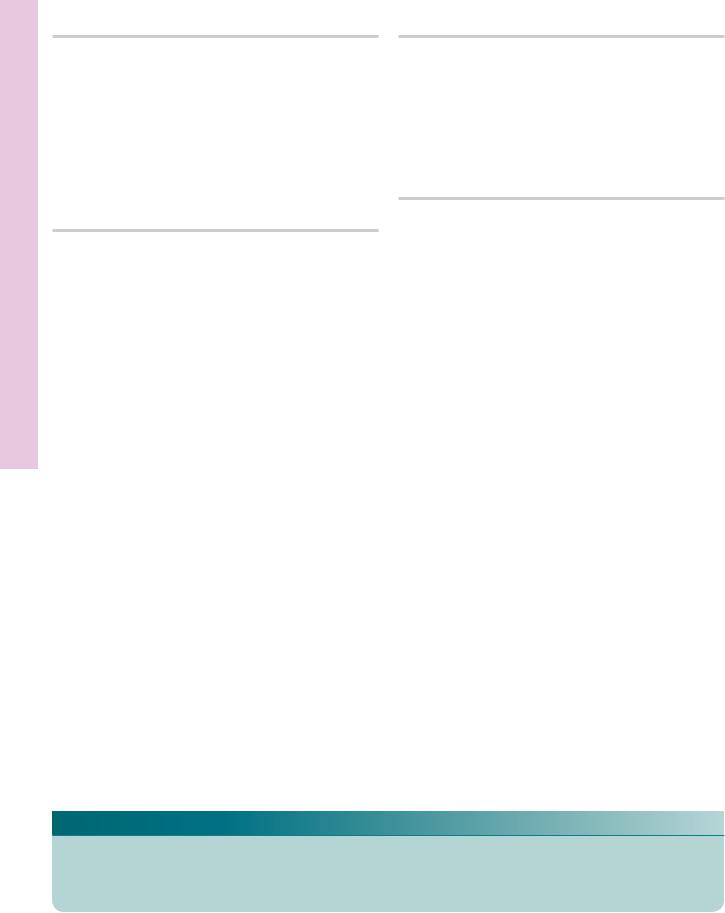

Blood Circulating and Marrow one • B4-5 PLATE

FIGURE 1. Bone marrow. Human. Paraffin section. ×132.

This transverse section of a decalcified human rib displays the presence of haversian canals (H), Volkmann’s canals (V), osteocytes (O) in their lacunae, and the endosteum (E). The marrow presents numerous adventitial reticular cells (A), blood vessels, and sinusoids (S). Moreover, the forming blood elements are also evident as small nuclei (arrows). Note the large megakaryocytes (M), cells that are the precursors of platelets. The boxed area is represented in Figure 2.

FIGURE 3. Blood smear. Human. Wright’s stain. ×270.

This normal blood smear presents erythrocytes (R), neutrophils (N), and platelets (P). The apparent holes in the centers of the erythrocytes represent the thinnest areas of the biconcave discs. Note that the erythrocytes far outnumber the platelets, and they in turn are much more numerous than the white blood cells. Since neutrophils constitute the highest percentage of white blood cells, they are the ones most frequently encountered of the white blood cell population.

FIGURE 2. Bone marrow. Human. Paraffin section. ×270.

This photomicrograph is a higher magnification of the boxed area of Figure 1. Observe the presence of osteocytes (O) in their lacunae as well as the flattened cells of the endosteum (E). The endothelial lining of the sinusoids (arrows) are clearly evident, as are the numerous cells that are in the process of hemopoiesis. Two large megakaryocytes (M) are also discernible.

FIGURE 4. Bone marrow smear. Human. Wright’s stain. ×270.

This normal bone marrow smear presents forming blood cells as well as erythrocytes (R) and platelets (P). In comparison with a normal peripheral blood smear (Figure 3), marrow possesses many more nucleated cells. Some of these are of the erythrocytic series (arrows), whereas others are of the granulocytic series (arrowheads).

KEY

A |

adventitial reticular cell |

M |

megakaryocyte |

R |

erythrocyte |

BV |

blood vessel |

N |

neutrophil |

S |

sinusoid |

E |

endosteum |

O |

osteocyte |

V |

Volkmann’s canal |

H |

haversian canal |

P |

platelet |

|

|

Blood Circulating and Marrow one • B4-5 PLATE

FIGURE 1 |

FIGURE 2 |

FIGURE 3 |

FIGURE 4 |